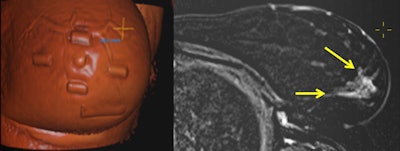

A 41-year-old patient with a large multifocal ductal cancer in the lower lateral quadrant of the left breast. Preoperative prone MRI showed a new large area of segmental nonmass enhancement in the upper quadrant of the same breast (not shown). A shaded, volume-rendered reconstruction image of supine MRI side by side to an axial subtraction image allows physicians to visualize the MRI-only detected lesions (arrows) in the surgical position and also navigate in real-time through the lesion and appreciate its extent as projected by a "crosshair" tool on the skin, also allowing measurements of distances in relation to the MRI-visible capsules positioned on the skin before scanning. All images courtesy of Dr. Sarianna Joukainen."In our opinion, the failure to show the true benefits of breast MRI is not only related to the microscopic tumor burden, but also to our inability to translate the information obtained from imaging in the prone position to surgery in the supine position," the study authors wrote.